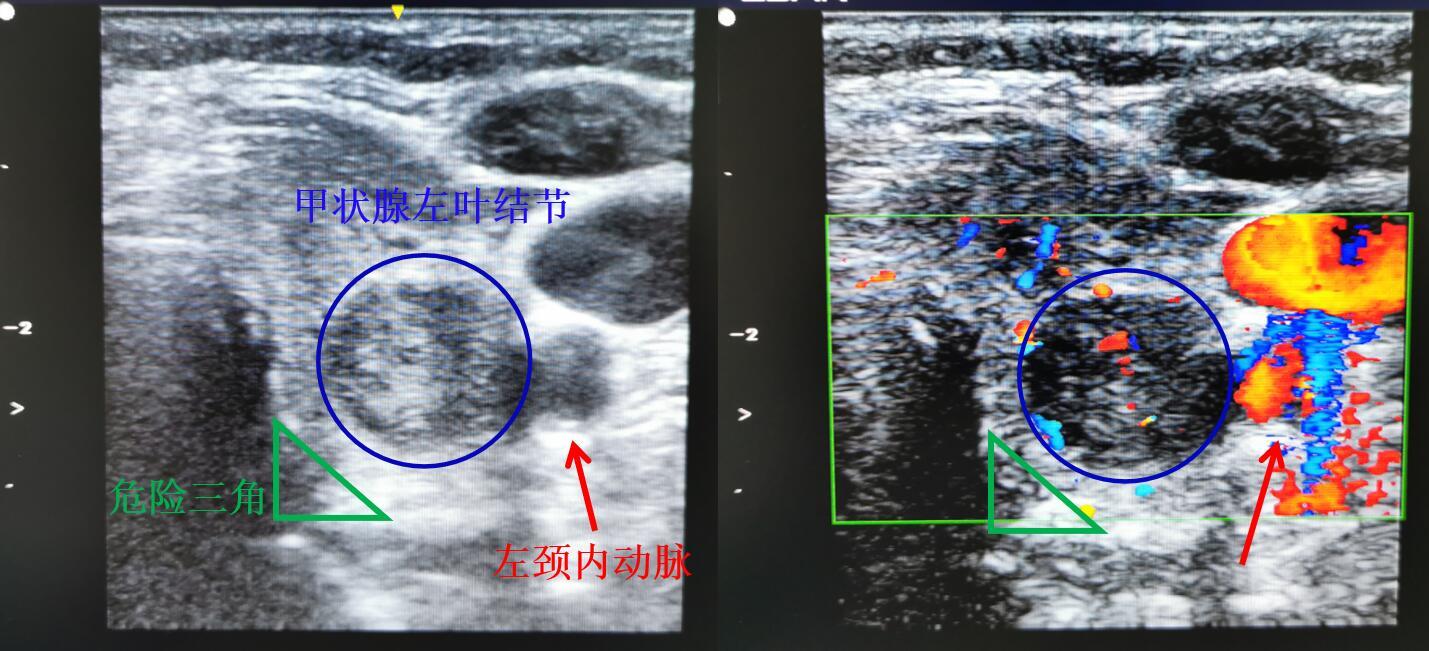

下图的甲状腺左叶结节紧贴着左颈总动脉,紧邻危险三角(喉返神经走行区